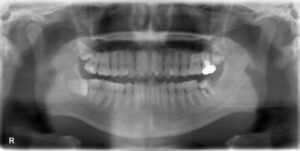

• 上下顎オールオン6症例

BEFORE AFTER 63歳男性/上顎6本・下顎6本 【治療内容】 全体的に歯が揺れてお食事がとりづらくなり、来院さ…